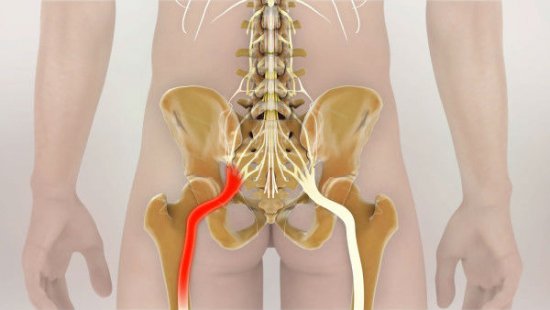

Компрессионная радикулопатия

Вызвана сдавливанием или растяжением корешков спинномозговых нервов из-за грыжи диска или уменьшения его высоты и, как следствие, расстояния между позвонками. Такая боль чаще ощущается как «поверхностная», распространяющаяся скорее в коже, чем в глубине тканей. Она резко усиливается при чихании, кашле, нагрузке на позвоночник. Именно такая боль ощущается как классический «прострел», отдающий по ходу нервного корешка.

Стеноз позвоночного канала

Возникает из-за грыжи диска, протрузии (выпячивания) его части в позвоночный канал или появления секвестра — отслоившейся части диска. Так или иначе сдавливается образование под названием «конский хвост» — корешки самых нижних спинномозговых нервов, иннервирующих нижние конечности. Боль при этом распространяется вдоль хода нервного корешка, от поясницы к стопе, появляется и в покое, и при ходьбе, усиливается при разгибании позвоночника и уменьшается при наклоне вперед.